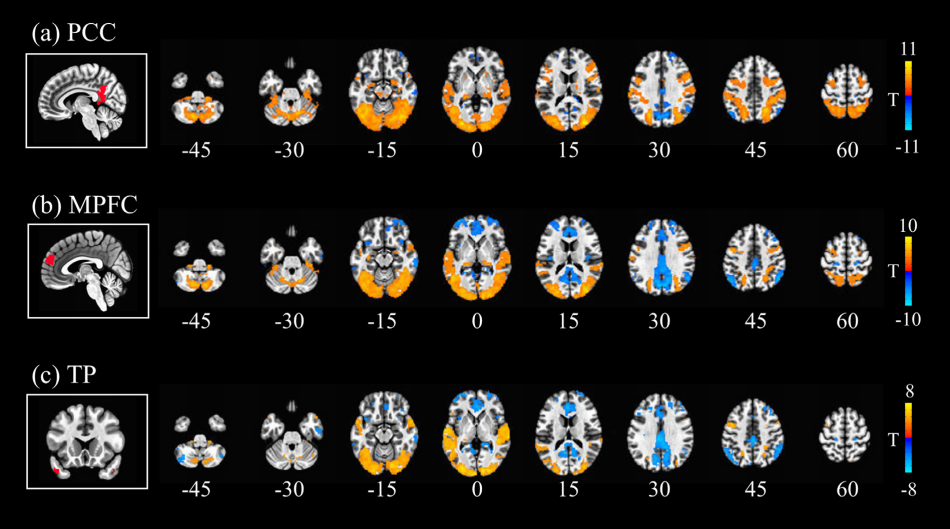

这篇发表于神经科学影像领域顶刊 NeuroImage 上的研究的主要目的是为了探寻个性化推荐短视频类成瘾行为的神经机制。整篇论文分为了两部分,第一部分是问卷调查,第二部分是主要的神经影像学研究。

然后,研究者找了 30 名 19-30 岁大学生,使用 fMRI 比较被试在观看 GV(generalized videos,一般视频)和 PV(personalized videos,个性化视频)两类视频时 BOLD(大脑血氧水平依赖)信号的变化。

这里的 GV 可以理解为用户在登录抖音账户前,系统分发的非个性化推荐的视频,PV 则是算法根据用户喜好给用户推荐的个性化视频,BOLD 信号反映了不同脑区的活跃水平。

简单来说,就是研究被试在看个性化推荐和普通短视频的时候,哪些脑区显著激活,哪些又没有显著激活。

通过这部分研究,研究者发现了个性化推荐短视频特别容易让人上瘾的两大机制:

第一,是观看个性化推荐视频时,大脑默认网络出现了激活功能分离,即涉及当前情境和精神状态的子系统被显著激活,但与思考未来有关的子系统没有显著激活。

这其实就是看短视频时大家特别沉浸,觉得时间一下子就溜走了的原因:我们被吸引着只关注了当下的刺激,而忽视了之后还需要做的事情,

第二,才是原文中关于多巴胺的内容:两类视频都会激活大脑黑质(SN),但个性化推荐视频还会激活腹侧被盖区(VTA),而 SN 和 VTA 都与多巴胺的分泌有关。

这仅仅意味着在个性化推荐的加持下,短视频对大脑奖赏系统的激活更为强烈。

浙江大学的一项功能性核磁共振成像研究为我们揭示了短视频与成瘾之间的关联(如图所示)[3]。该研究对浙江大学的 153 位抖音用户进行了一次问卷调查。其中,约 45.8% 的调查参与者存在轻中度的抖音上瘾问题,且有 5.9% 的人对抖音严重上瘾。统计分析显示,自控能力越差,上瘾程度越高。现代常见的焦虑情感可能会促使人们将小视频视为逃离压力的避风港,而缺乏自控力的人可能更难从这种逃避中抽离出来,进而对短视频产生过度的依赖。

默认模式网络的三个节点与大脑其他区域的功能性连接图示。

(a)在观看推荐算法所推荐的视频时,后扣带回皮质(posterior cingulate cortex)与初级视觉、听觉区域,以及一部分顶叶区域的功能性连接增强。

(b)相同情况下,内侧前额叶皮层(medial prefrontal cortex)与前扣带回皮质(dorsal anterior cingulate cortex)等其他区域的功能性连接减弱。

(c)颞极在颞上回内的功能性连接增强,与楔前叶、腹内侧前额叶皮质(ventromedial prefrontal cortex,vmPFC)等诸多区域的功能性连接减弱。

默认模式网络(default mode network)活动的降低是大脑在集中注意力时最明显的信号。默认神经网络主要由内侧前额叶皮质,后扣带回皮质和角形脑回(angular gyrus)组成,是一个横跨整个大脑的大型神经网络。在人们无事可做、胡思乱想的时候,默认神经网络会变得非常活跃。同时,它也参与包括环境观测、自我参照、社会认知等其他复杂的认知功能。

自我参照(self-referential processing)指一个个体在思考跟自我有关的信息时的认知过程,这包括了追忆过去、计划未来以及体会当下。在短视频中,个性化推荐的内容往往与用户喜好、兴趣、经验有比较高的契合,因此,它们会触发观看者的自我参照过程。在这个过程中,负责投射过去与未来的内侧颞叶子系统的活跃度会降低,处理当下觉知的背内侧前额叶皮质的子系统的活跃度会升高。于是,人们关于过去和未来的思维活动被抑制,注意力完全集中在当下。与此同时,默认模式网络与初级视觉皮层、初级听觉皮层以及额顶叶网络(frontoparietal network)的沟通被加强。初级感觉皮层解码和加工基础的视觉和听觉刺激。额顶叶网络则负责维持注意力与短期记忆。这些网络的密切合作调动了过去积极的观影体验,这些体验自上而下地调控了注意力的分配,使用户的注意力更多地集中在视频提供的视觉和听觉刺激上。

后扣带回皮质是默认模式网络的重要枢纽,其主要功能之一是平衡向内与向外的注意力。向内注意力(internally oriented attention)指的是对内部思考的专注,向外注意力(externally oriented attention)指的是对外部刺激的关注。推送视频会使后扣带回皮质与负责短期记忆的额上回(superior frontal gyrus)、额中回(middle frontal gyrus)的连接增强,使观看者的注意力从外部转向内部,同时通过整合短期记忆中储存的视频信息,让大脑对视频信息进行更深度、更有意义、更高级的处理。

在一部分脑区变得更加活跃的时候,另一部分脑区的活动出现了减弱。背前扣带回皮质 、尾状核(caudate),还有一部分的丘脑(thalamus)负责注意力分配以及对抑制的控制(inhibition control)。当我们在看短视频时,这些区域的活动同时减弱,彰示了自控能力的降低。同时,它们与默认模式网络连接的减弱还会降低个体对自控力的把控和对意识的觉察,使人们在观看短视频时更加沉浸忘我,无法自拔。